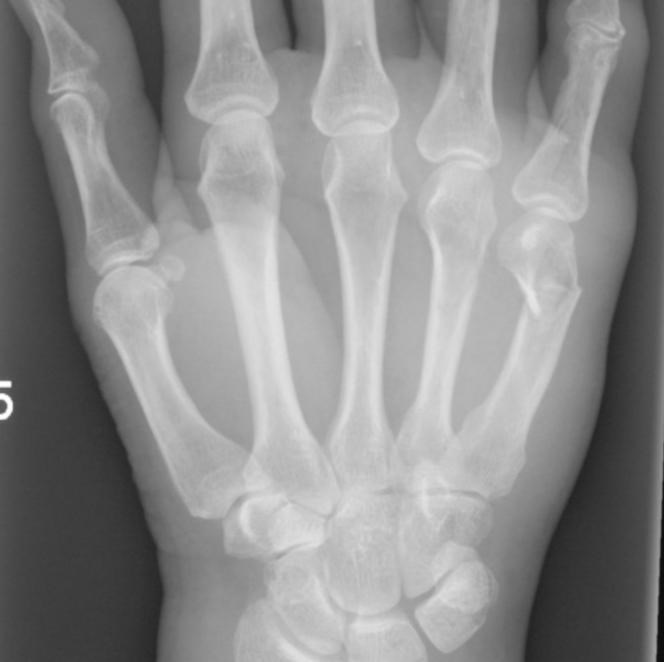

Osteit/osteomyelit

Allmänt

Osteit/osteomyelit innebär djup infektion i ben och/eller benmärg. Hematogen spridning eller Direkt spridning från omgivande mjukdelar eller närliggande led förekommer (oftast hos småbarn) men är ovanligt pga. den effektiva barriär som benhinnan utgör. Därför är det vanligast att en osteit uppkommer efter att en fraktur, en skruv eller något annat föremål skadat periostet.

På händerna är det vanligast med osteit i fingertopparna efter att patienten gått lång tid med lågintensiv infektion i anslutning till kring naglarna. I övrigt kan en osteit förekomma på vilken lokal som helst efter öppen fraktur eller att bakterierna spridits via osteosyntesmaterial eller annan kirurgi.

Osteit är liksom övriga handinfektioner förhållandevis ovanliga såvida man inte har systemsjukdom som påverkar immunförsvar eller perifer blodcirkulation. Att de är ovanliga gör dem inte banala, tvärtom är det ett allvarligt tillstånd och inte slutar en osteit i ett finger med amputation.

Fynd

Osteit kan ge sparsamt med symptom. Låggradig värk och viss svullnad uppkommer men rodnad och ömhet kan vara diskret, särskilt om benet är täckt av lite tjockare mjukdelar.

SR, CRP, leukocyt antal och andra prover ger också svag och sen indikation då den lokala infektionen endast ger svag allmän inflammation i kroppen. Diagnosen ställs istället via röntgenbildernas utseende. Ofta får röntgen undersökningen upprepas och man ser då suddigt avgränsade mörka områden som ibland kantas av en periostal reaktion.

Det tar vanligen 2-3 veckor för att röntgenförändringarna att utvecklas. En snabbare och tydligare diagnos kan man få genom MR eller Leukocyt scintigrafi men de ger dålig information efter trauma.